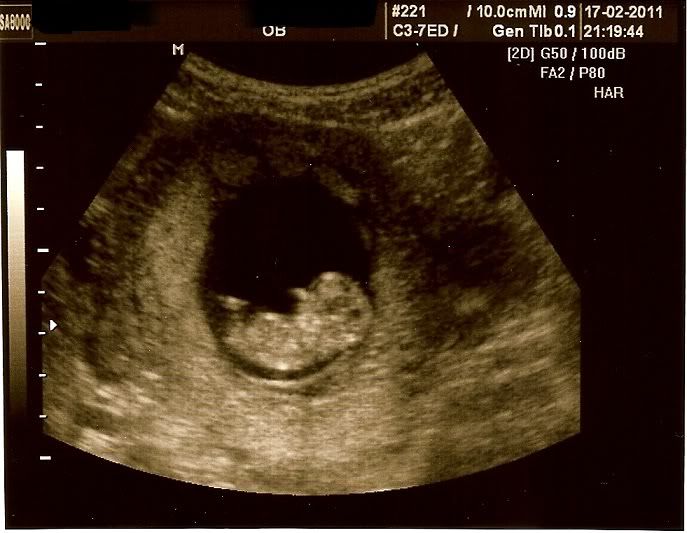

Het heeft even geduurd, omdat ik zo ziek was van de buikgriep, maar hier is dan eindelijk de scan van mijn echo!

Mooi he....